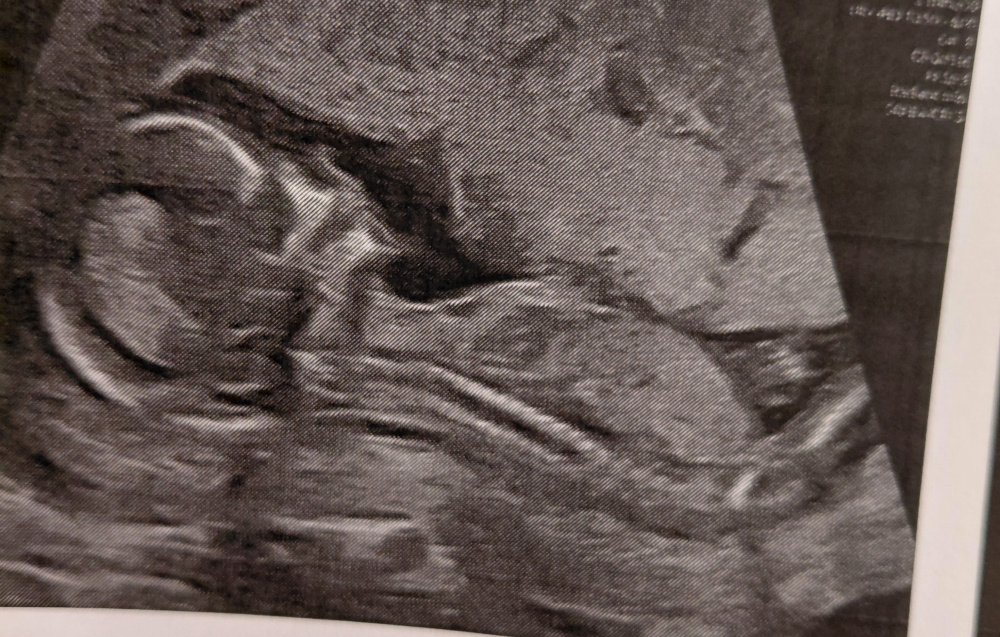

Was glaubt ihr, was für ein Geschlecht laut nub theorie ?